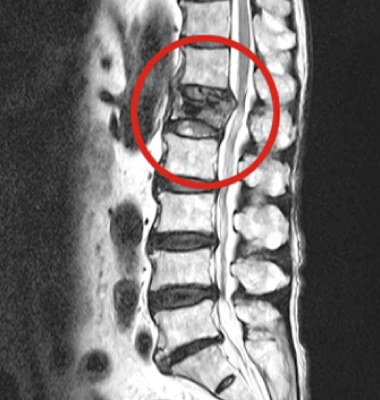

척추뼈가 외부 충격으로 인해 찌그러지고 골절되는 질환입니다.

척추뼈의 경우 팔과 다리뼈의 골절과는 다르게 뼈가 찌그러지듯이 납작해지기 때문에 '압박골절'이라 표현합니다. 외형상 변화가 없이 때문에 발생된 후에도 잘 느끼지 못한 채 방치하는 경우가 많습니다.

압박 골절된 척추뼈 (2016.03.18)

단, 골절이 심하여 척추뼈가 신경을 심하게 압박하는 경우나

척추뼈의 골절이 심한 파열 골절의 경우는 수술적 치료가 필요할 수 있습니다.

수술적 치료는 척추뼈가 움직이지 않고 신경을 자극하지 않도록 하는 고정술을 주로 시행합니다.